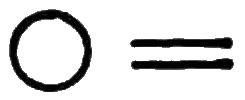

Symp. Each febrile paroxysm is of three periods or stages—the cold, the hot, and the sweating stage, and these occur in regular succession. The cold stage commences with great languor and aversion to motion; a sense of coldness down the back soon follows; then the extremities become cold, the fingers shrunken, and the nails blue; the skin assumes that peculiar condition which is commonly known as ‘goose-skin,’ the patient shivers, his teeth chatter, and he is glad to draw close to the fire or envelop himself in blankets. After this state of things has continued for a greater or less time, the heat of the surface begins to return, the patient has flushings and becomes warmer and warmer, and ultimately the whole surface is of a dry burning heat; intense thirst, restlessness, severe headache, and sometimes delirium, characterise this second or hot stage. After this stage has continued for some time, another change comes over the patient; moisture appears on the face and forehead, the harsh and hot skin becomes soft, and at last a copious sweat breaks out over the whole surface. This is the third or sweating stage, and after it has passed, the several functions of the system return to their ordinary condition. The paroxysm may return daily (QUOTIDIAN AGUE); or every other day (TERTIAN A.); or every fourth day, including that of the first attack (QUARTAN A.).